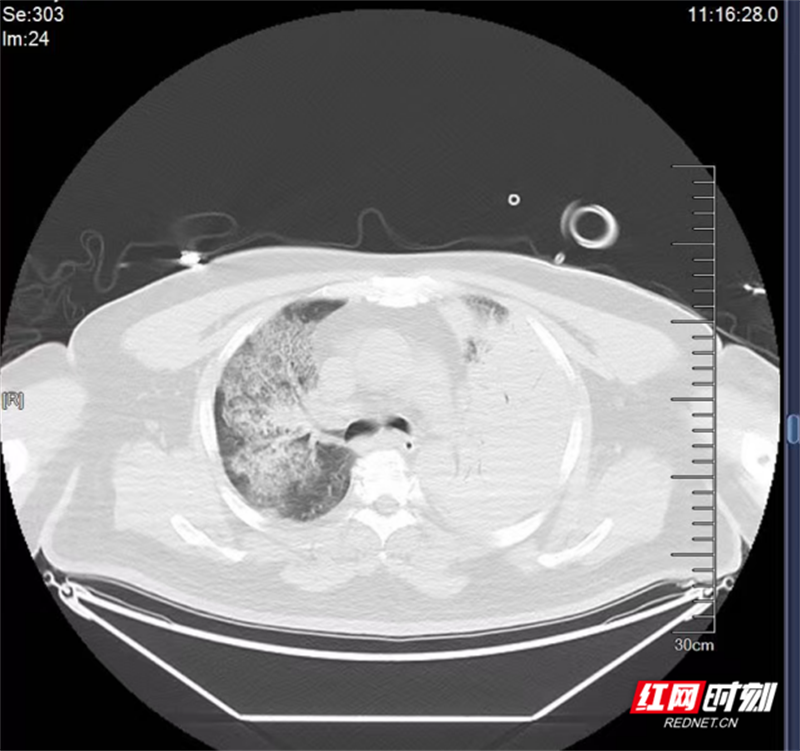

患者刘某(化名)因突发高热、呼吸急促,于外院治疗两天后病情加重,被紧急转入郴州市第四人民医院重症医学科。经无创呼吸机辅助通气,其缺氧症状仍未改善,血氧饱和度持续下降,主管医生立即进行气管插管,改为有创机械通气,并完成CT检查。结果显示,患者左肺实变,右肺亦存在大面积病灶,残留肺功能不足三分之一,确诊为重症肺炎合并重度ARDS、呼吸衰竭。

治疗前。